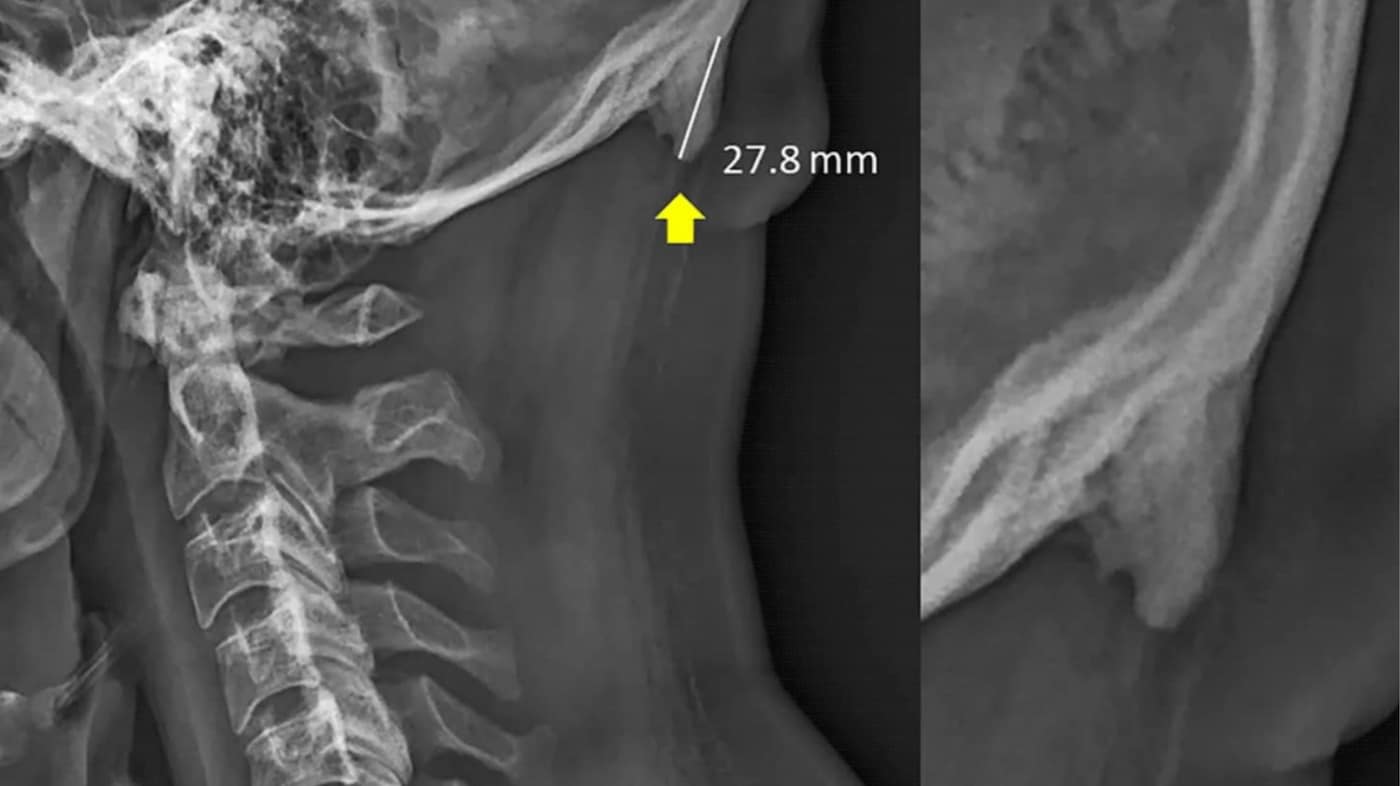

Science & Tech / NewsScience & Tech / NewsNo, despite reports, mobile phones do not make you grow hornsFake horny news, peopleShareLink copied ✔️June 21, 2019June 21, 2019TextGünseli Yalcinkaya Yesterday, the Washington Post published an article claiming that young people are developing horns at the back of their skulls, as a result of poor posture from texting. What if phones... but they make us literal demons. The unlikely proposition comes from a recently unearthed report by two researchers at the University of Sunshine in Queensland, David Shahar and Mark Sayers, who found that young people are more likely to have enthesophytes (AKA bony lumps that grow as a result of environmental, chemical or genetic factors) at the base of their skulls than people over the age of 30. But, as with most of the things on the internet (anyone remember smartphone pinky?), it’s all speculation. Fake news, people. The initial report from 2016 details that in a group of 218 people between the ages of 18 to 30, 41 per cent of them had small enthesophytes at the back of their skulls, which Shahar and Sayers speculate (emphasis on ‘speculate’) could have to do with the “increased use of hand-held technologies from early childhood”. The most important thing here is that the study doesn’t actually measure phone use, and only reflects on the age associated with the rate of horny nubs. Really, researchers are just hypothesising, so of course it being a young pool of participants, phones and social media usage is the conclusion they draw. And so we can throw this in the trash – a follow-up report from 2018, which looked at four 13 to 16 year old boys with enthesophytes, found no correlation between genetics and the development of bony growths. No link is made to phone use. I repeat, there is no link between using your phone and growing horns. Nada. As people online have been pointed out too, the data in the study at times directly contradicted itself. At one point, we’re shown a graph that says men had fewer enlarged EOPs than women, but saying in the text says the opposite. Elsewhere, ages of participants are inconsistent, from 18-29s to 18-30s. People are questioning how it even got through the peer-reviewing process in the first place. Yes, there’s such a thing as human error and we’re okay with a typo here and there, but it makes this report much harder to trust. Utimately, your phone isn’t turning you into a horned demon straight from the hellmouth just yet. Of course, this doesn’t distract from the fact that almost all of us have compulsive notification addiction or that your screen light is giving you wrinkles. Escape the algorithm! Get The DropEmail address SIGN UP Get must-see stories direct to your inbox every weekday. Privacy policy Thank you. You have been subscribed Privacy policy Expand your creative community and connect with 15,000 creatives from around the world.READ MORECould the iPhone 15 Pro kill the video game console?Is Atlantis resurfacing? Unpacking the internet’s latest big conspiracyEscentric MoleculesMolecule 01 + Champaca is Escentric Molecules’ latest sultry scentElon Musk’s Neuralink has reportedly killed 1,500 animals in four yearsCould sex for procreation soon be obsolete?Here are all the ways you can spot fake news on TikTokWhy these meme admins locked themselves to Instagram’s HQ Why did this chess-playing robot break a child’s finger?Twitter and Elon Musk are now officially at warAre we heading for a digital amnesia epidemic?Deepfake porn could soon be illegalMeet Oseanworld, the internet artist tearing up the metaverse rulebookEscape the algorithm! Get The DropEmail address SIGN UP Get must-see stories direct to your inbox every weekday. Privacy policy Thank you. You have been subscribed Privacy policy